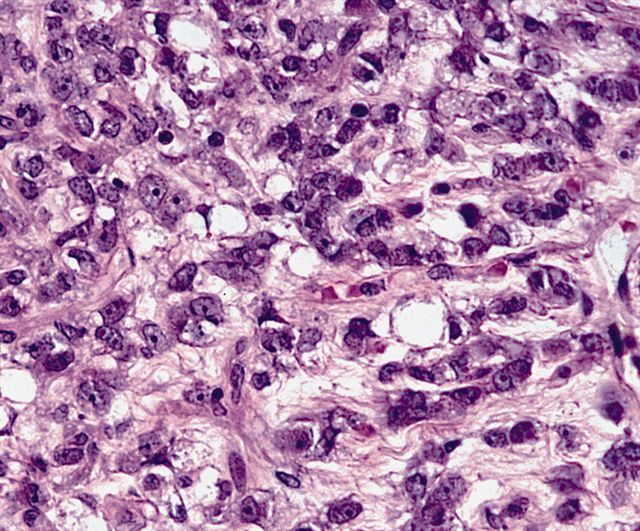

- High grade

- Hypercellular solid sheets of back to back cells with round cell or primitive cytomorphology in > 5% of the sampled tumor

- Cells can have a small amount of hypereosinophilic cytoplasm, a finding of no clinical significance but of significant diagnostic confusion, especially in a limited sample

- Pitfalls and tips

- High grade tumors are so cellular that you can typically walk across nuclei in a high power field without stepping in matrix

- When in doubt, especially in a small sample, pursue molecular testing (typically fluorescent in situ hybridization) for FUS gene rearrangement